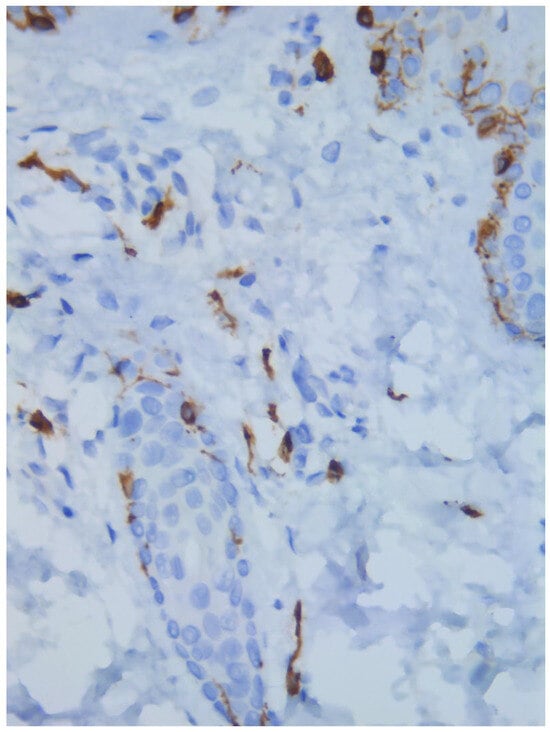

A skin biopsy showed basal cell hyperpigmentation and a chronic superficial perivascular inflammatory infiltrate that also affected the periphery of the hair follicles (Figure 6). Tryptase stain reached figures of up to 29 mast cells per high-power view (67/mm2), and CD117 up to 46 mast cells per high-power view (92/mm2), mostly surrounding the hair infundibulum (Figure 7), although some interstitial mast cells were also observed (Figure 8). PAS stain was negative for yeasts or fungal hyphae. Abdominal ultrasound study did not detect any anomalies. The bone scintigram detected mild non-specific osteoblastic lesions in the L5, S1 and sacroiliac joints (pending further study).

Figure 8. Mast cell infiltration (CD117 ×400).